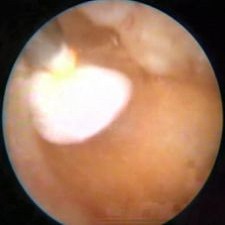

Odstranění drobných polypů a myomků

Popis nálezu

Odstranění drobných útvarů (děložních polypu či myomků) z dutiny děložní je zpravidla jednoduchým výkonem. Za optimálních podmínek netrvá zpravidla déle jak 10 minut. Takto odstraněný útvar je samostatně zasílán k posouzení a histologickému rozboru.

Zařazení nálezu

• Věk pacientky: 55 let

• Datum: Leden 2014

• Druh: Odstranění

• Lékař: MUDr. Petr Kovář